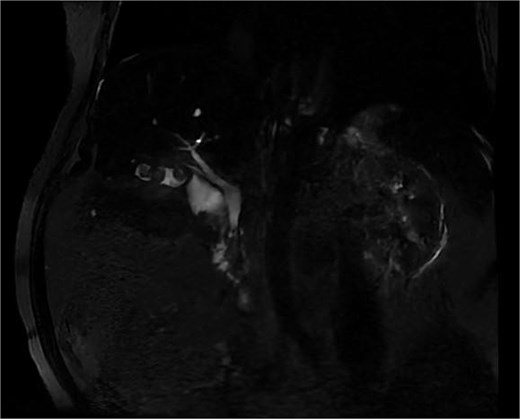

Initial abdominal computed tomography revealed a macro-lithiasic gallbladder with partially sclero-atrophic wall and nodular thickening of 16 mm, raising suspicion of neoplastic degeneration. Magnetic resonance cholangiography demonstrated two distinct formations in the gallbladder region, non-communicating, initially interpreted as double gallbladder with a single cystic duct (Fig. 1). The first formation appeared partially sclero-atrophic, while the second, located in the hepatogastric space, was distended with apparent lithiasic content and thickened walls. Moderate dilatation of the main and intrahepatic bile ducts was noted without identifiable lithiasic obstruction.

Biliary MRI showing an image mimicking a double gallbladder with a single cystic duct and an intravesicular macrolithiasis.